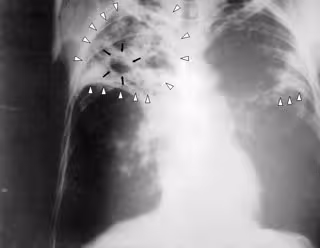

Tuberculosis